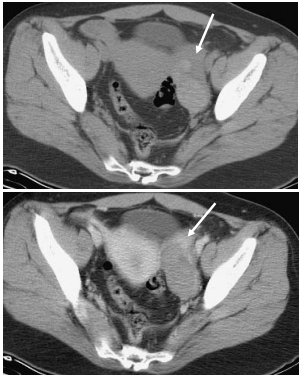

73 28 歲張太太結婚三個多月,一向健康狀況良好。昨天突然下腹部劇烈疼痛、陰道出血(vaginal bleeding)。 醫師檢查發現她的骨盆腔內積血,有緊急狀況而為她做電腦斷層攝影,所見如下圖。她最可能患有 何病?

(A)卵巢囊腫(ovarian cyst) (B)子宮外孕(ectopic pregnancy) (C)子宮內膜異位症(endometriosis) (D)卵巢癌(ovarian cancer)